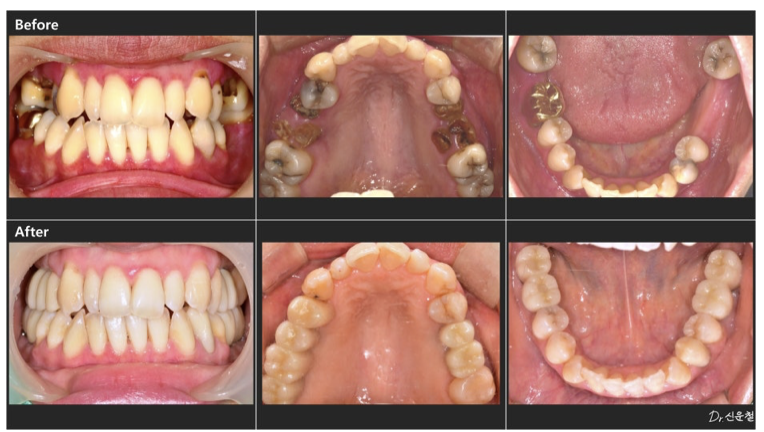

실제로 내원하신 30대 여성 환자분도

“아프진 않아요.”라고 말씀하셨습니다.

촬영일 250327

하지만 정밀 검진 결과, 깊게 진행된 사랑니 충치 뿌리만 남은 치아

잇몸뼈가 녹아 흔들리는 어금니 가 확인되었습니다.

통증이 없었던 것뿐,

문제는 이미 상당히 진행된 상태였습니다.

만약 웨딩 촬영 직전 증상이 악화됐다면

발치를 먼저 해야 하는 상황이었을 수 있습니다.

앞니 배열만이 아니라 어금니 충치, 보철 색감, 잇몸 라인까지

전체적인 밸런스를 함께 봐야 합니다.

디에스다솜치과에서는

단순히 “보이는 앞니”만이 아니라

웃는 순간 전체가 자연스러운지를 기준으로 진단합니다.